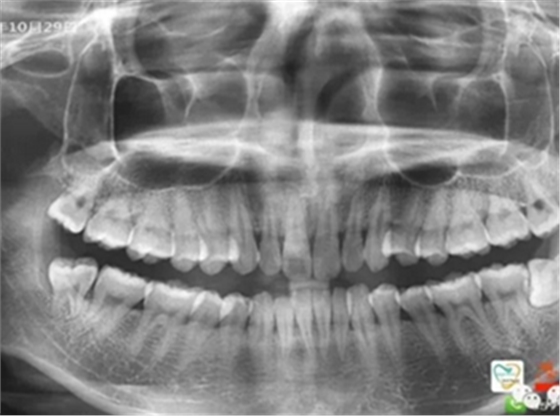

再比如智齒:

由于智齒的生長位置特殊,導(dǎo)致了拔除難易不同,如智齒出現(xiàn)橫著長或者靠近牙神經(jīng)的話,則難度會較高,一般人只需拍個口腔全景片,但相對于智齒靠近神經(jīng)管的情況,還可能需要拍CT,這都很考驗(yàn)牙醫(yī)的技術(shù)。